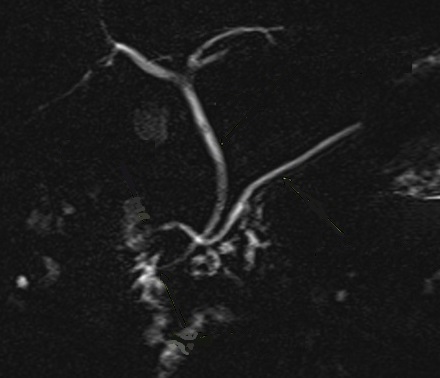

Image

radiologique CPRM d'une pancreas divisum de type II

. Le canal pancreatique principale est s'aboucher

pans la papille mineur duodenum . La voie biliaire

principale est s'aboucher au papille majeur duodenum

et le canal pancreatique ventral est totalement

absent |

Image radiologique CPRM d'une pancreas divisum

de type III. Le canal pancreatique principale est

s'aboucher pans la papille mineur duodenum . La voie

biliaire principale est s'aboucher au papille majeur

duodenum et.le canal pancreatique ventral est en

joindre avec une brache du canal dorsal . |